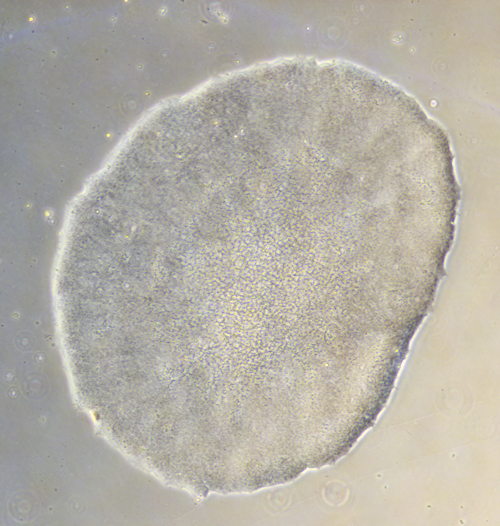

The European Bank for induced pluripotent Stem Cells (EBiSC) aims to:

- Provide quality-controlled, disease-relevant research-grade iPSC lines, data and cell services

Ludovic Vallier was jointly based at the Cambridge Stem Cell Institute and the Wellcome Sanger Institute. His laboratory studies the basic mechanisms controlling differentiation of human pluripotent cells into pancreas, lung, gut and liver cells. His overall objective is not only to investigate molecular mechanisms of differentiation but also to generate cell types for clinical studies and for cell based therapy.